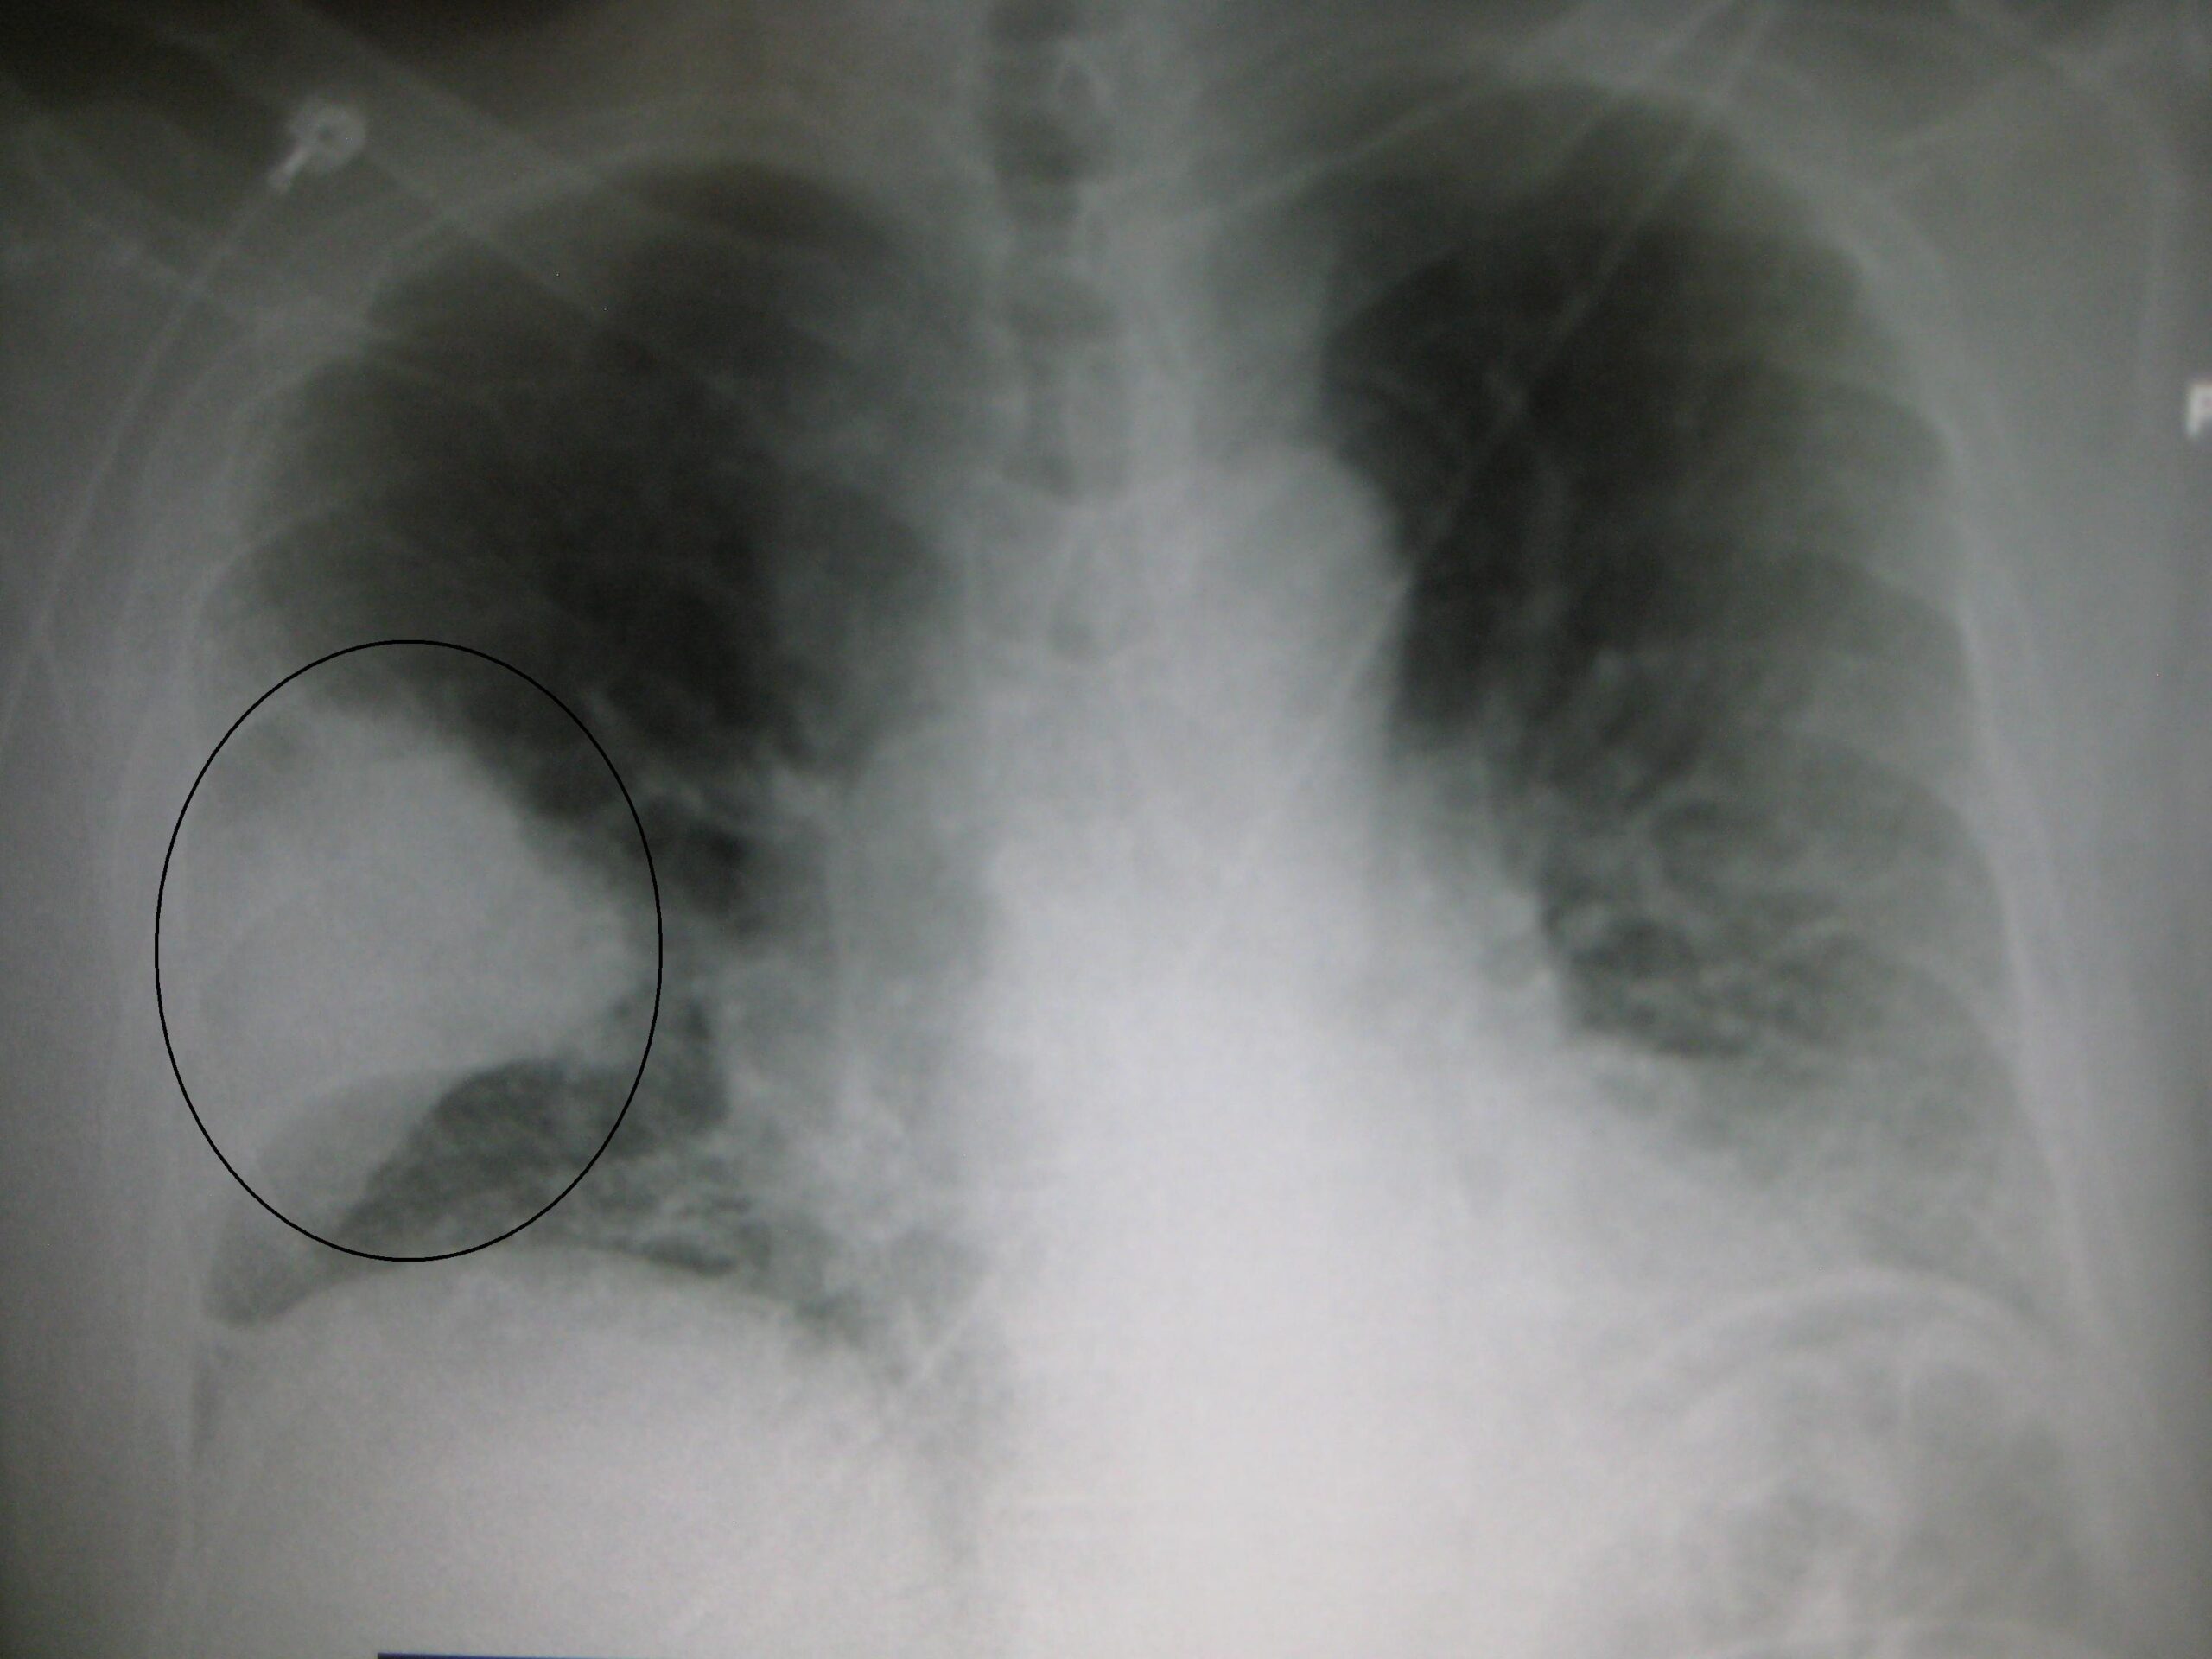

Sonntag, 05. Juni 2016 ab 13:30 Uhr: Die Zeit ist da, um die Behandlung einer bestimmten Lungenentzündung, der CAP, zu ändern: Eine Lungenentzündung (= Pneumonie) ist eine Infektion der Lunge und wird in der Regel durch Bakterien verursacht. Eine Pneumonie kann mild verlaufen und nur Husten verursachen, oder schwer verlaufen und Husten mit Schleim und Mukus, Fieber von 39° C oder noch höher, Atemnot, Schmerzen beim Atem, einen schnellen Herzschlag, Zittern und Schüttelfrost verursachen. Eine Lungenentzündung kann eine ernsthafte Erkrankung sein. Sie sollten so schnell wie möglich Ihren Arzt/Ihre Ärztin aufsuchen, falls Sie denken, dass Sie eine Pneumonie (= eine Lungenentzündung) haben könnten. Einige Patienten können einen schweren Verlauf haben und starke Antibiotika und Behandlung in einem Krankenhaus benötigen.

Der Ausdruck ambulant erworbene Pneumonie (CAP) wird speziell verwendet, um sie von der nosokomial erworbenen Pneumonie (HAP) zu unterscheiden, weil deren Behandlungen unterschiedlich sind. Und die Zeit ist nun da, um die Behandlung der ambulant erworbenen Pneumonie (CAP) zu ändern. Zwei randomisierte kontrollierte klinische Studien und eine Meta-Analyse aus 2015 haben gezeigt, dass eine kurze Gabe (5-7 Tage), täglich und in moderater Dosierung, von systemischen Corticosteroiden bei hospitalisierten Patienten mit ambulant erworbener Pneumonie (CAP) zu besseren klinischen Ergebnissen führt, einschließlich weniger Behandlungsversagen, weniger Todesfälle und kürzere Zeitspanne bis klinische Stabilität. Das gilt insbesondere für Patienten mit schwerer Lungenentzündung.